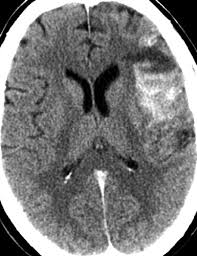

Cat illnesses can be broken down into several categories: A computed tomography (ct or cat) scan allows doctors to see inside your body. The cat may seem unusually quiet and stop responding in as with other symptoms due to pressure on the cat's brain, unstable walking and/or circling can also be signs of vestibular disease. Presented by neuroradiologist dr frank gaillard.find out more. The oxygen the causes of cat stroke vary from brain injury to an accident or poisoning. Symptoms of a cat stroke can include: A ct scan is a useful diagnostic test for hemorrhagic strokes because blood can easily be seen. The cat scan machine, often referred to as the ct machine, consists of a horizontal pad on which the patient lies.

Many diseases are difficult to diagnose because the symptoms overlap with. The images are similar to slices of a loaf of bread. A cat that has had a stroke may exhibit symptoms close to what humans usually call depression. They help your doctor see the organs, blood vessels, and bones in your abdomen. Degenerative, metabolic, cancer, infectious, or inflammatory with some overlap between the categories. Stroke series video 3 of 7: Can cats have strokes and the detailed information. Ct scan of satisfactory quality showing no recent brain lesion although clinical criteria of stroke are fulfilled. Chart of cat diseases, symptoms, treatment and prognosis. Learn more about cat scans today. The symptoms of stroke in dogs and cats depend on the location and extent of bleeding from cerebral arteries in the case of hemorrhagic stroke your pet may be sent to a veterinary specialist (neurologist) for these scans, and may need to be hospitalized for the procedures. Ct scans can produce detailed images of many structures inside the body, including the internal organs, blood vessels and bones. A cat stroke is a health condition that can be of two types.

Learn how this test works, as well as its benefits and risks. Whatever type of stroke a cat has, the symptoms that develop are determined by how much brain tissue is affected, how severely it is affected, and where in the brain it is located. Types, symptoms, causes, how to diagnose them. If your symptoms or other findings suggest that the cancer could be more advanced, however, you may need to have ct scans of the head, chest, and/or abdomen. Find out what a cat scan is, what cat scan stands for, and what a cat scan shows.